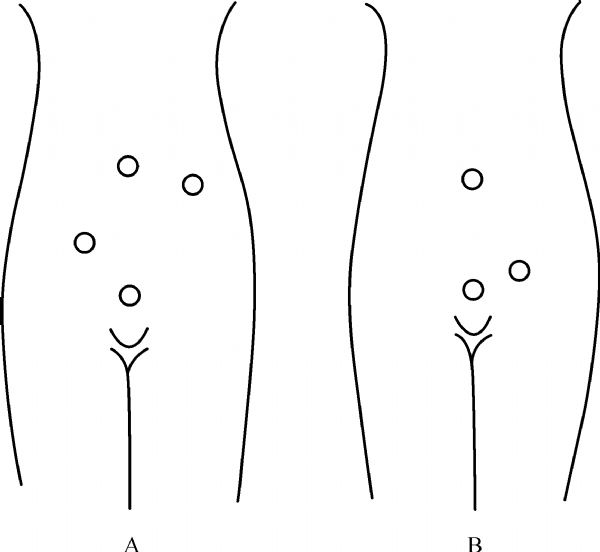

Hongyi Cui

Single incision laparoscopic surgery (SILS) is a novel minimally invasive surgical technique that is gaining popularity around the world. One of the most commonly performed procedures is single incision laparoscopic cholecystectomy (SILC). Most reported techniques utilize special purpose-made access port and articulating instruments, rendering the procedure costly and difficult to learn. This article provides a stepwise description of SILC technique using all straight instruments without the need for a special port. It aims to shorten the learning curve for surgeons wishing to adopt a safe and cost-effective SILC technique to their practice.